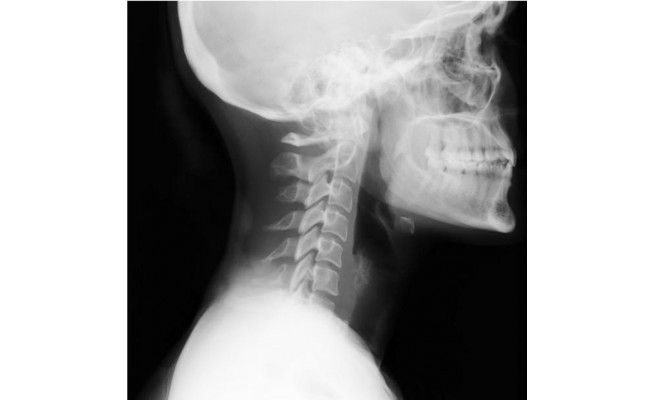

Le bilan et le traitement présentés mettent en avant des spécificités indissociables de l'exercice professionnel de la patiente, à savoir une inversion de courbure cervicale liée à l'action de chanter qui représente l'élément incontournable à prendre en compte par le praticien.

The assessment and the treatment presented highlight specific features inseparable from the patient's professional practice, namely an inversion of cervical curvature linked to the singing action which represents the essential element to be taken into account by the practitioner.